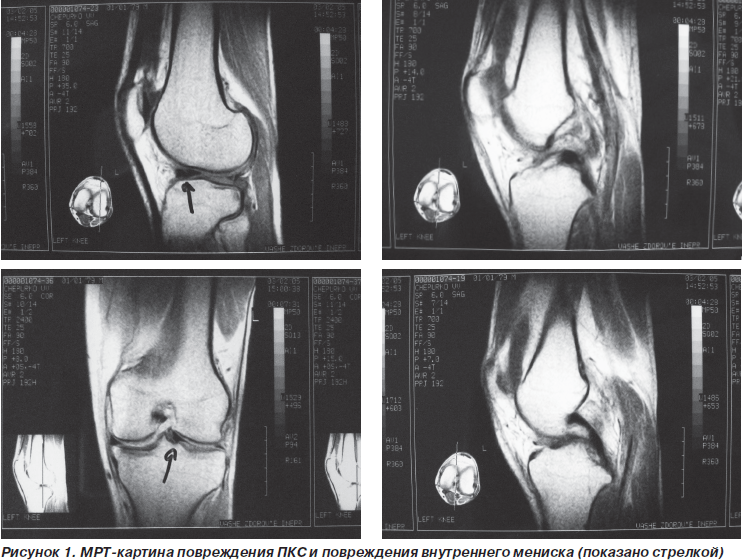

По данным артроскопии разрывы передней крестообразной связки (ПКС) были выявлены у 16 больных. По данным МРТ этих пациентов картина полного разрыва имела место только у 3 из них (18,75 %). У 10 пациентов (62,50 %) по данным МРТ состояние было оценено как неполный разрыв. Еще у 3 больных (18,75 %) повреждений передней крестообразной связки при МРТ-исследовании обнаружено не было.

Разрывы внутреннего мениска по заключению МРТ были у 13 пациентов. При артроскопии у 12 из них разрыв был подтвержден. Всего при артроскопии выявлены 15 разрывов внутреннего мениска. То есть у трех больных повреждение внутреннего мениска на МРТ замечено не было. У данных пациентов имели место лоскутные разрывы внутреннего мениска.

В то же время при диагностике повреждения крестообразной связки, которая расположена внутрисуставно, МРТ-исследование не обладает столь высокой чувствительностью. Это связано с тем, что не всегда имеет место дислокация связки в полости сустава, вокруг связки наблюдается перифокальный отек синовиальной оболочки. Эти образования дают сигнал высокой интенсивности и затрудняют визуализацию места разрыва. При застарелых повреждениях в ряде случаев имеет место регенерат связки, который не выполняет ее функции. Однако при МРТ он дает сигнал, не всегда отличающийся от нормального, что затрудняет интерпретацию изображения.